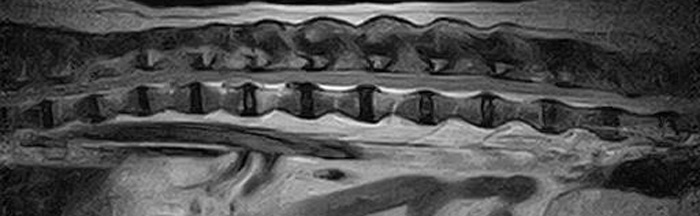

犬の多発性胸腰部椎間板ヘルニアのMRI検査

市外の先生からダックスちゃんの腰の痛みの精査依頼でMRI検査のご紹介がありました。検査結果から多発性胸腰部椎間板ヘルニアを認めました。その後かかりつけの先生のもとで内科治療となりました。